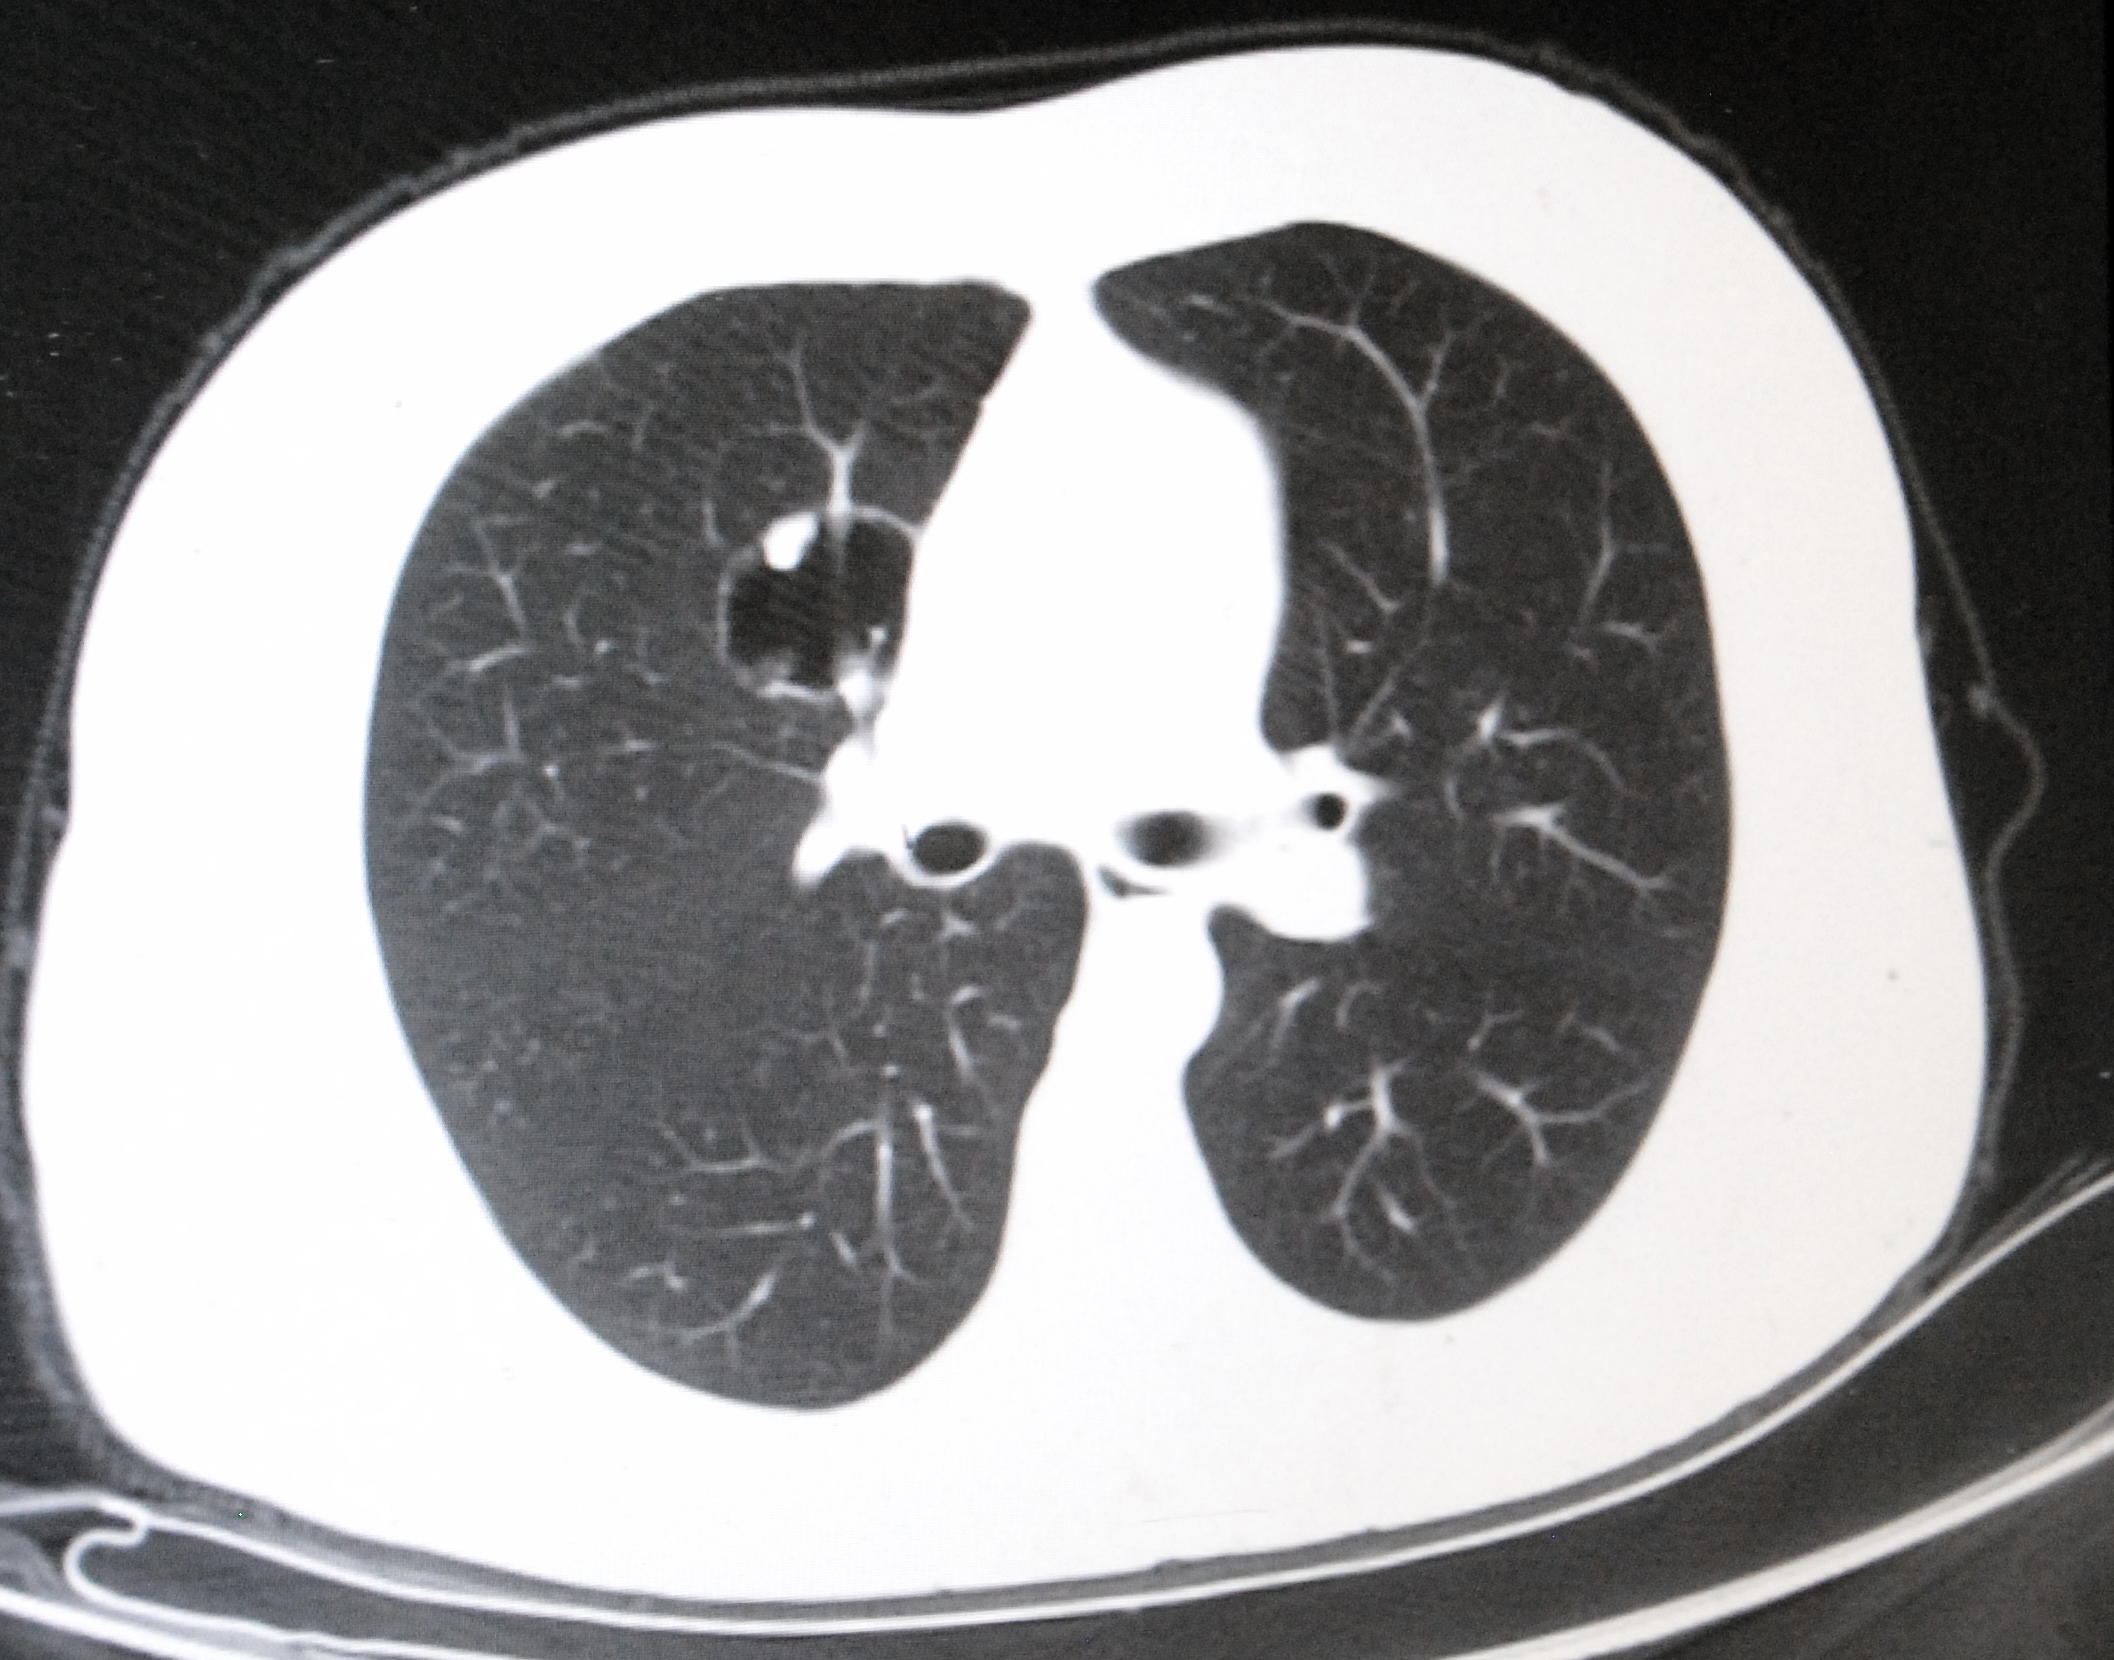

HIs first surgery of the day is an asymptomatic middle-aged patient with an incidental finding[1] of a large bronchiogenic cyst in the right middle lobe.

On the CT scan, it looks like an egg-yolk with solid material within a fluid-based cyst. The initial suspicion is a possible aspergilloma but this presumptive diagnosis is eliminated during surgery based on tumor appearance.

The second case is a young patient with a GGO (ground glass opacity) in the right upper lobe. A needle biopsy confirms that the mass is a malignancy, an adenocarcinoma. This surgery is also smooth and uneventful.